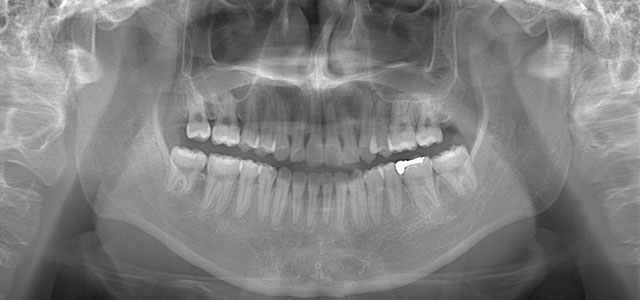

矯正前 パノラマX線

矯正後 パノラマX線

主訴 凸凹の歯並びを治したい。虫歯が多い。

年齢 10代男性

治療法 上下顎マルチブラケット装置

抜歯の有無 上顎左右第一大臼歯、上顎左側第一小臼歯、下顎左右側第一大臼歯

治療期間 2年5ヶ月